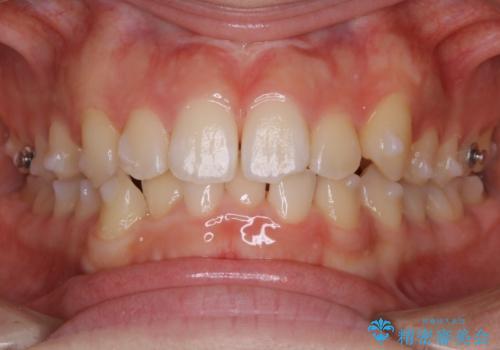

- 上の前歯のすきっ歯と下の前歯のガタつきを主訴にご来院されました。

噛み合わせの改善も同時に進めつつ、主訴の部分も効率的に治していくためマウスピース装置でゴムかけを行いながら治療を進めていきました。

正中離開(すきっ歯)

真ん中の歯が左右に開いてしまい隙間ができてしまう状態を「正中離開」といい、俗にすきっ歯と呼ばれています。

隙間を埋めていく方向に歯を移動させることで改善していくケースが多く、比較的治りやすい不正咬合のひとつとされています。

しかしながら、歯が捻じれていたり、噛み合う歯との位置関係によっては治療が難しくなる場合があります。